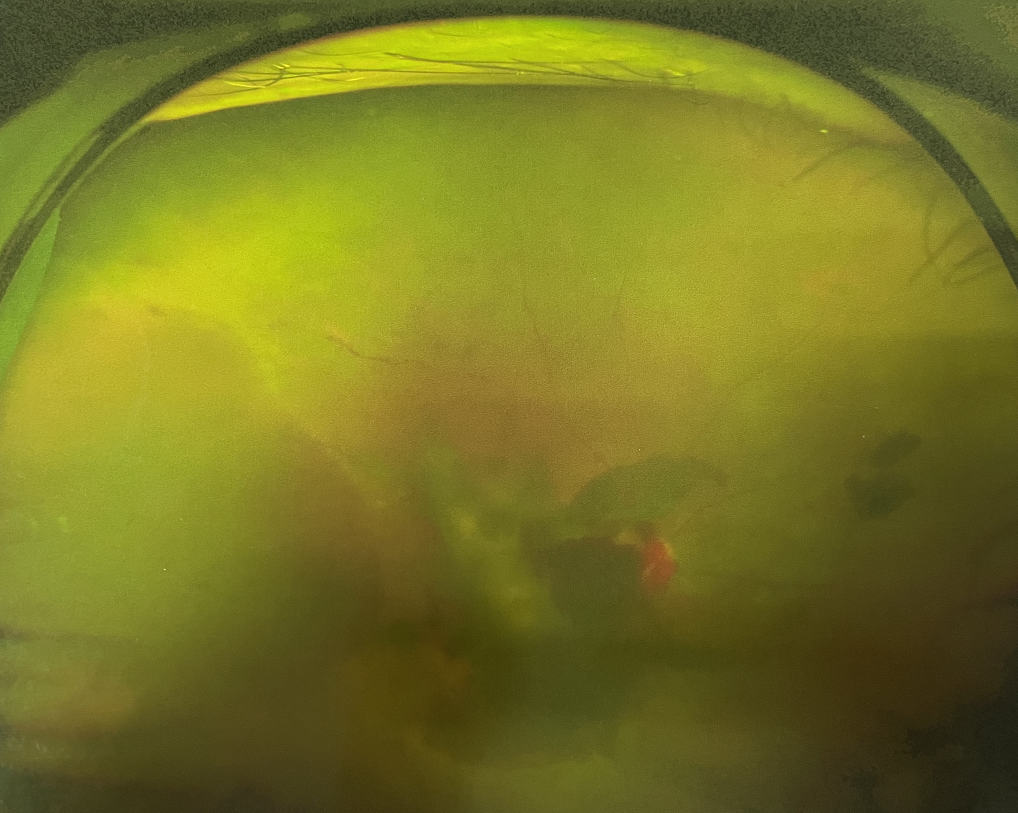

右眼術(shù)前

眼底病專科張小虎醫(yī)生檢查后,診斷王女士為“雙眼玻璃體積血、雙眼糖尿病視網(wǎng)膜病變V期”。(V期即5期,纖維增生期,出現(xiàn)纖維膜,可伴視網(wǎng)膜前出血或玻璃體出血。)

張小虎醫(yī)生為王女士進(jìn)行右眼玻璃體腔注藥術(shù),3天后進(jìn)行右眼23G玻璃體切割術(shù)后視力有所提升。

4個(gè)月后王女士來院取硅油,取油后視力恢復(fù)到0.6。“當(dāng)時(shí)來的時(shí)候真的只能看到模糊的影子,特別害怕覺得完了,想說眼睛估計(jì)要瞎了,沒想到手術(shù)后視力竟然提升了,現(xiàn)在也看得比較清楚了。”王女士說到。

張小虎醫(yī)生表示,糖網(wǎng)病進(jìn)展到嚴(yán)重增殖期帶來的視力損傷往往是極其嚴(yán)重的,目前王女士右眼從術(shù)前0.02恢復(fù)到術(shù)后0.6,已屬十分難得。